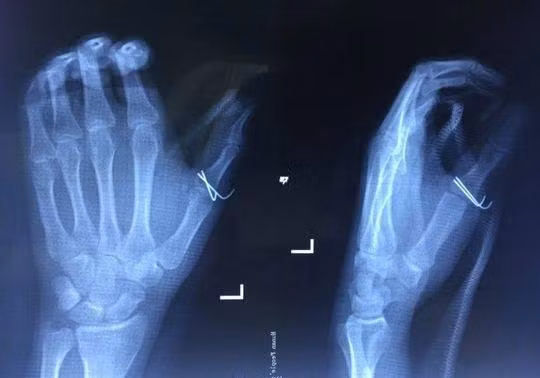

Ngay sau đó, anh Hòa đến bệnh viện để cấp cứu và được các bác sĩ cho biết, vết thương của anh tương đối nặng, rách, thủng khoảng 7cm ở miệng bàn tay trái, buộc phải khâu lại và băng bó điều trị.